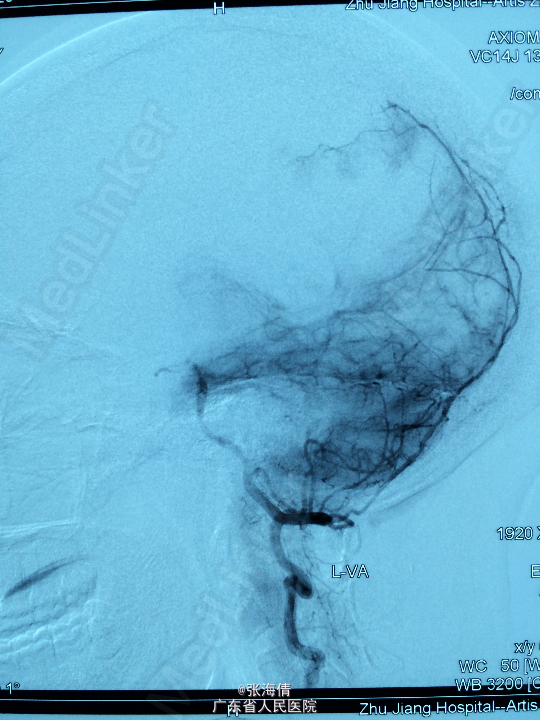

诊断:脑膜瘤 处理:先予DSA以明确肿瘤供血情况,术中脑膜瘤供血丰富,用PVA颗粒超选到供血动脉将其闭塞。后再择期在气管全麻下行脑膜瘤切除术。

术后病理提示:脑膜瘤,WHO I级,瘤组织浸润脑组织。免疫组化:Ki一67(<1%)(+),CK(一),GFAP(一),Vimentin(+),EMA(+),P53(一),ER(一),PR(一)。 讨论:脑膜瘤首选方法为手术切除,手术切除脑膜瘤是最有效的治疗手段,但是由于其供血经常较为丰富,故可先行介入栓塞供血动脉后再行切除,这样可以降低手术风险和手术难度,改善患者手术预后。